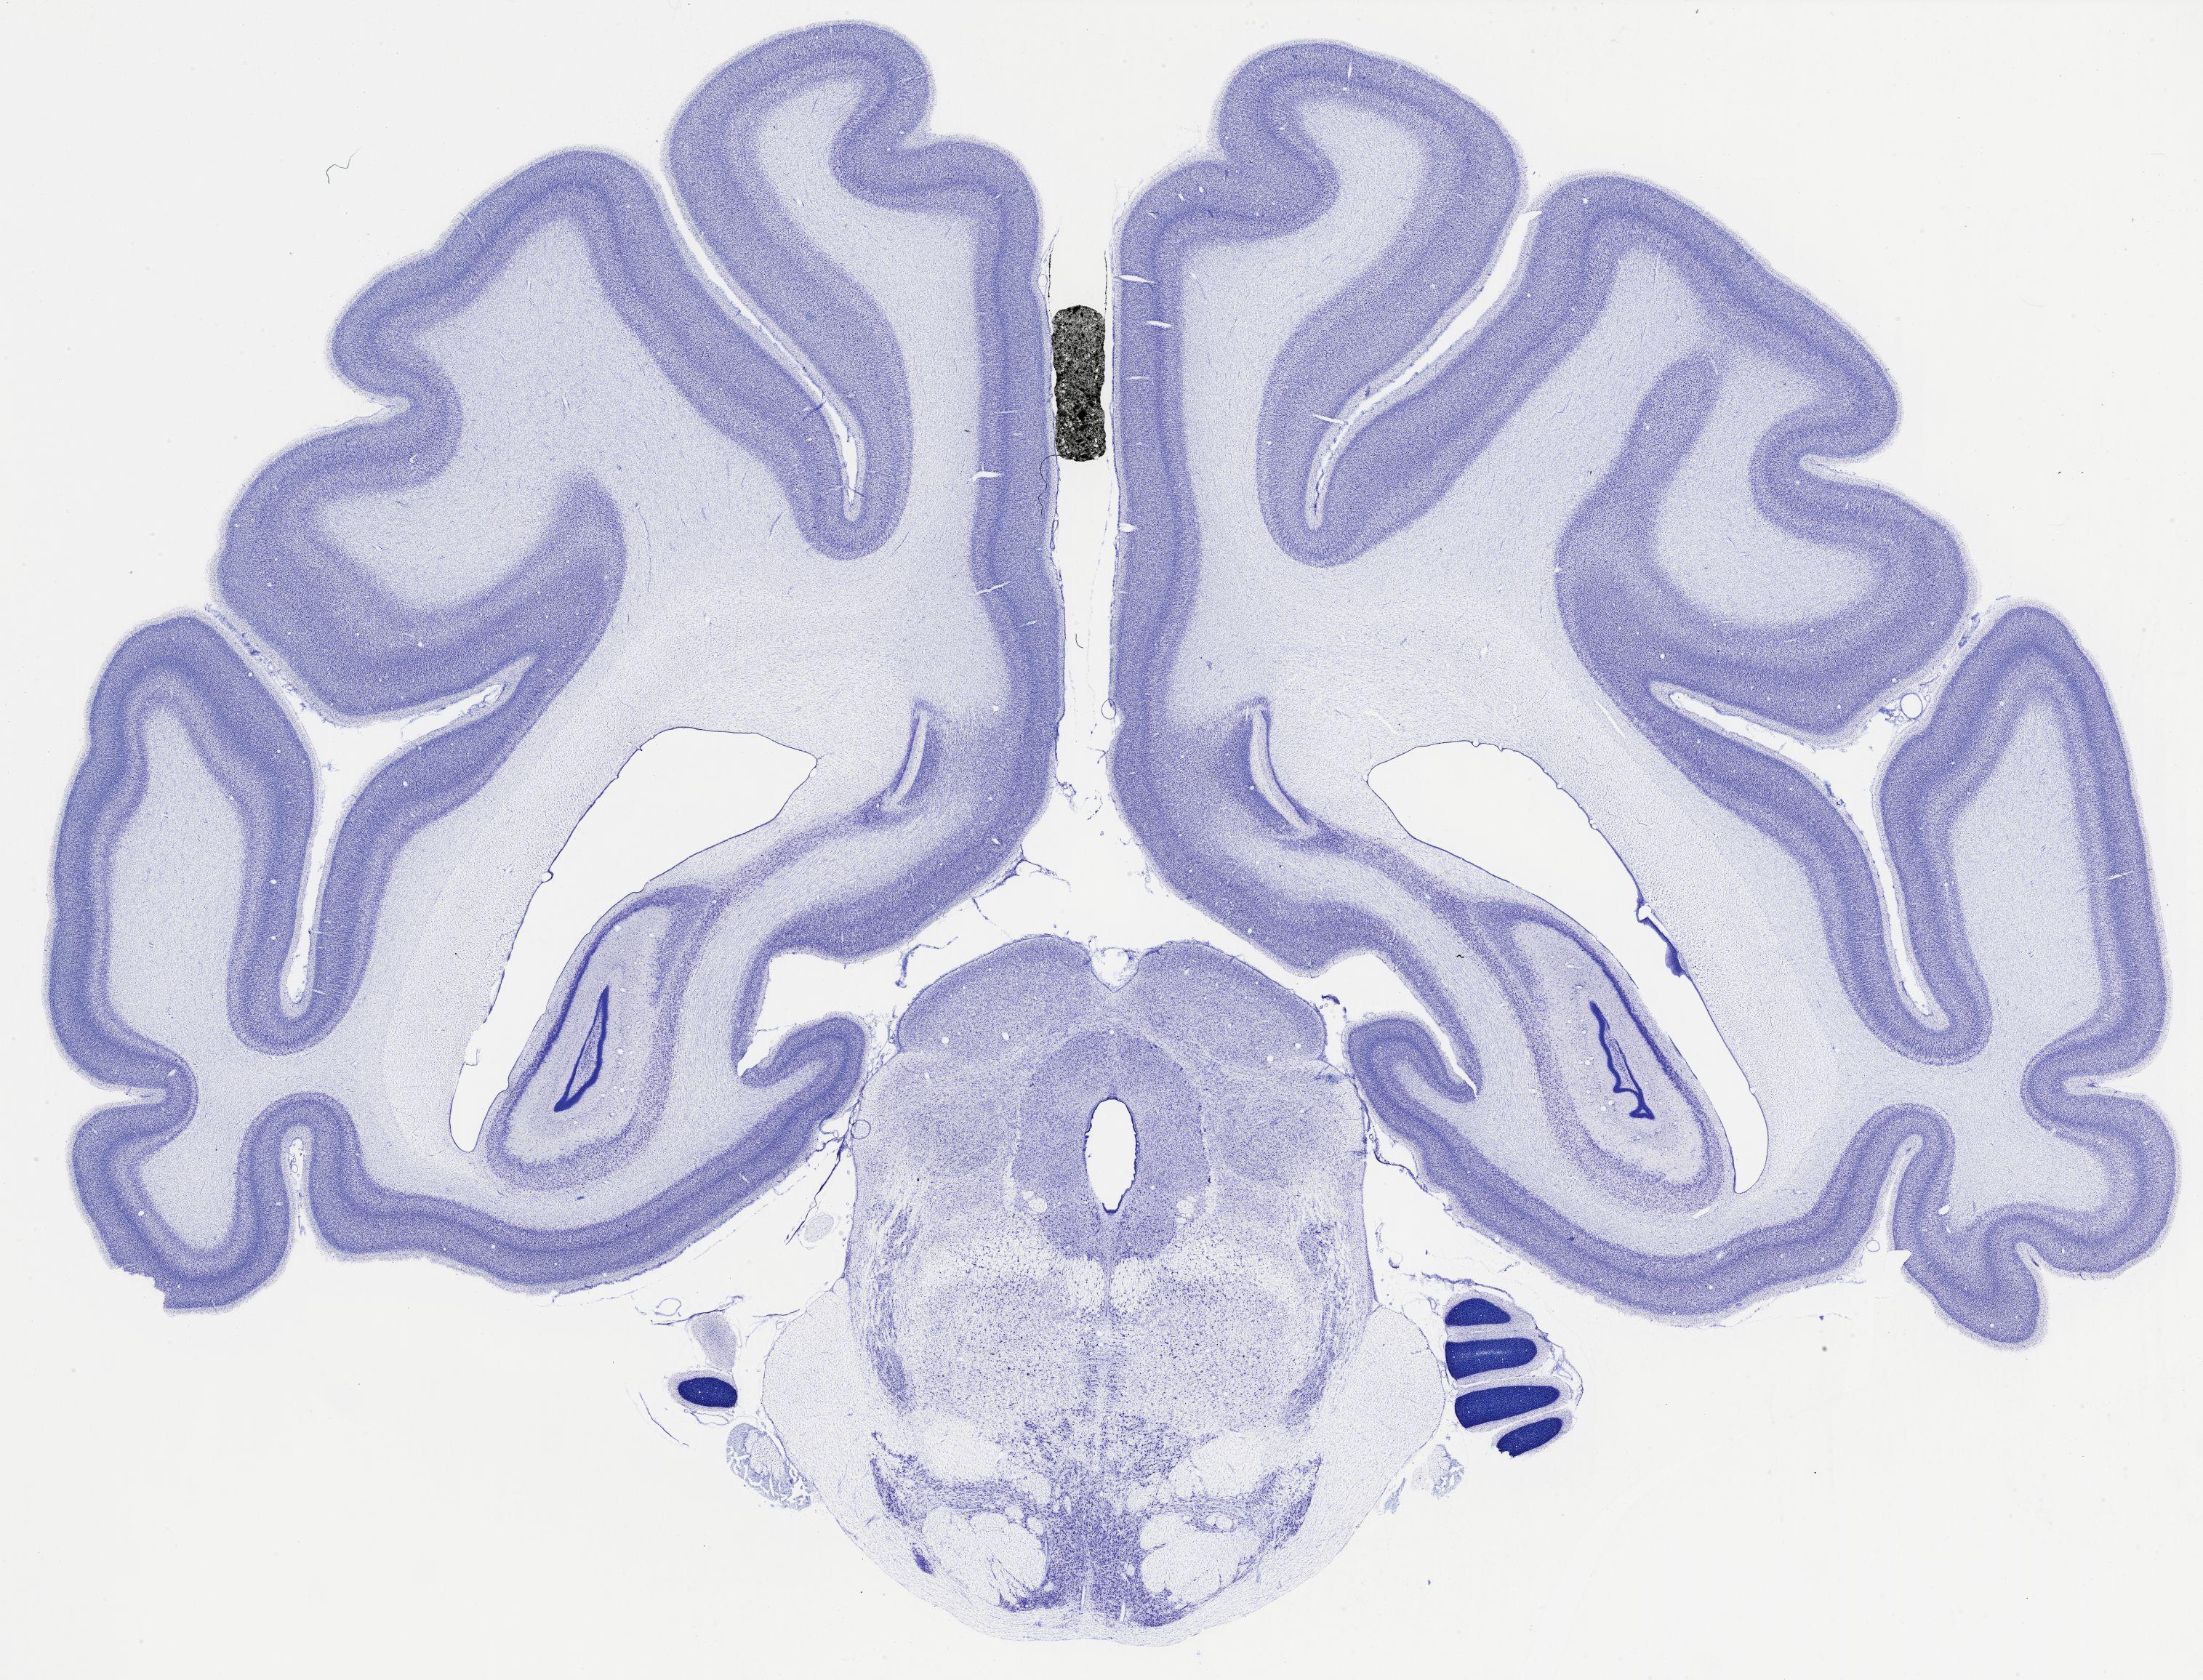

thumbnail

482